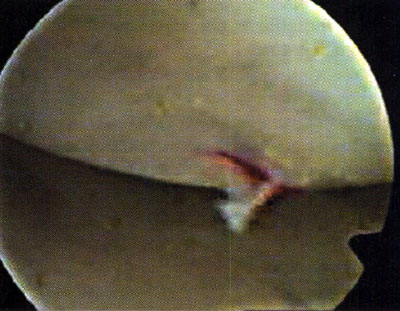

En 5 casos se comprobó, lesión condral tipo 1 de Noyes y Stabler (10), con una zona reblandecida a la palpación que nos orientó la exploración, diagnóstico y drenaje hemático con el palpador. En ningún caso la zona fue mayor de 20 mm de diámetro. Al realizar la punción con el palpador, se evacuó sangre roja fresca con la sensación de caer en una zona cavitaria. No se observó en ningún caso abombamiento de la zona reblandecida. En todos los casos, una sola perforación nos pareció suficiente.

Todas las lesiones correspondieron a la zona de apoyo no protegida por el menisco.